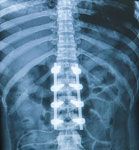

Minimally Invasive Spinal Trauma Fixation